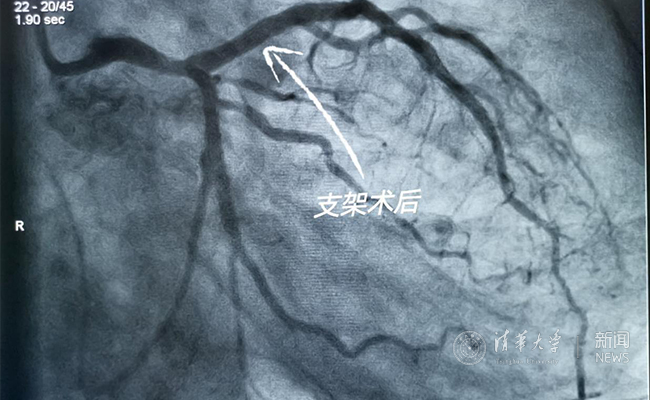

2019.05国产冠脉生物可吸收支架在华体会娱乐平台第一附属医院正式启用

作为北京地区首家正式引入国产冠脉生物可吸收支架单位,5月20日,华体会娱乐平台第一附属医院(北京华信医院)心脏中心主任苗立夫团队顺利完成该院首例生物可吸收支架植入。